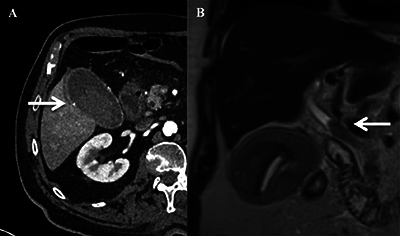

Teaching point: Cystic artery pseudoaneurysm is a rare condition that should be considered in patients with unexplained abdominal pain, a history of gallbladder disorders, or signs of hemorrhage, and can be diagnosed by Doppler ultrasound.